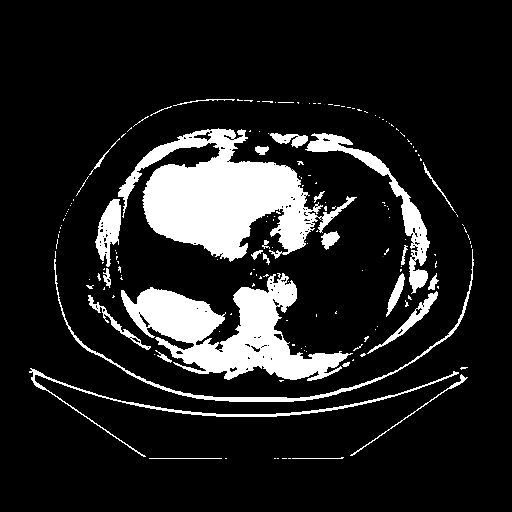

Original NATIVE CT scan (input)

Full window (WL 1023.5, WW 4095 β†’ Low βˆ’1024, High +3071)

Actual HU range: [-1024.0, 3071.0]

Original VENOUS CT scan